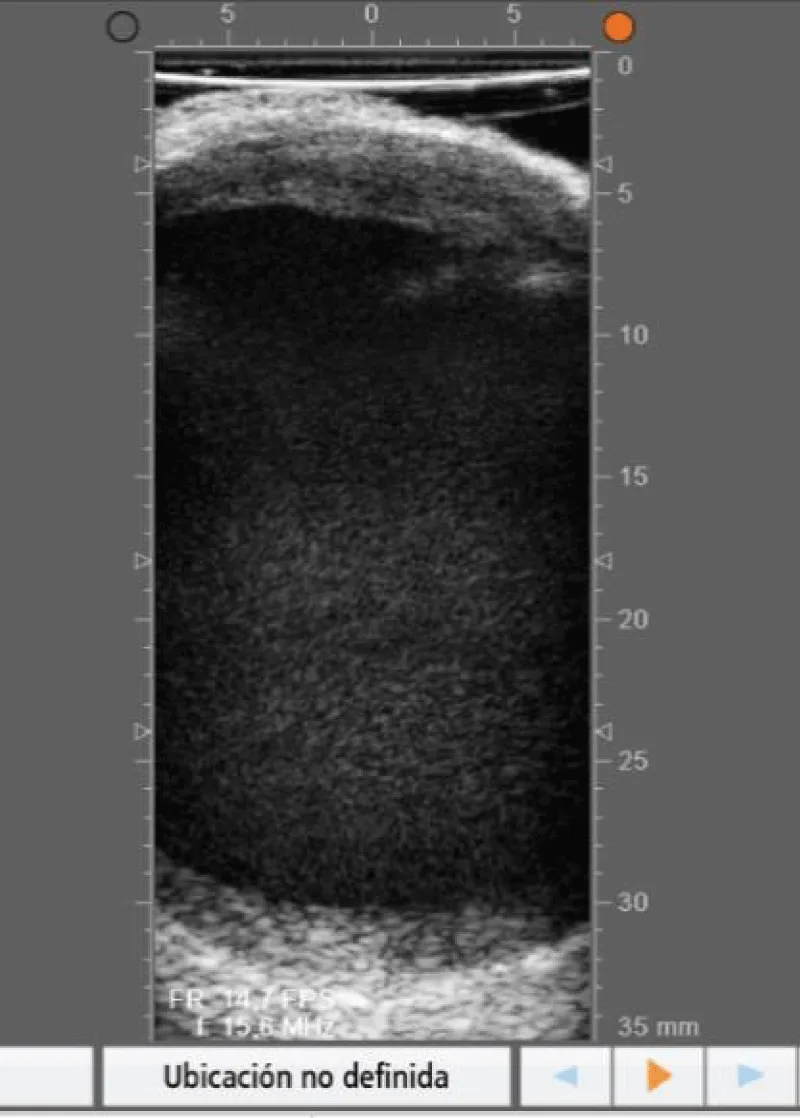

The goal of the first step of the protocol is to perform a global evaluation of the vascular damage of the patient, paying special attention to the state of the aortic wall (where cannulation, cross-clamping site in case of surgery with extracorporeal circulation, and lateral clamping to perform the proximal anastomosis, need to be chosen) (Figures 4,5) and also to locate the ideal place to perform the anastomosis between the graft and the coronary artery (Figures 6-8).

Download Image

Figure 4: Echography showing an aortic with an intact anterior wall.

Figure 5: Echography showing an aortic wall with a plaque in the anterior wall.

Figure 6: Anterior descending coronary artery with 2,4mm diameter and an intact arterial wall.

Figure 7: Anterior descending coronary artery with a plaque in the posterior wall.

Figure 8: Coronary artery with a stent.